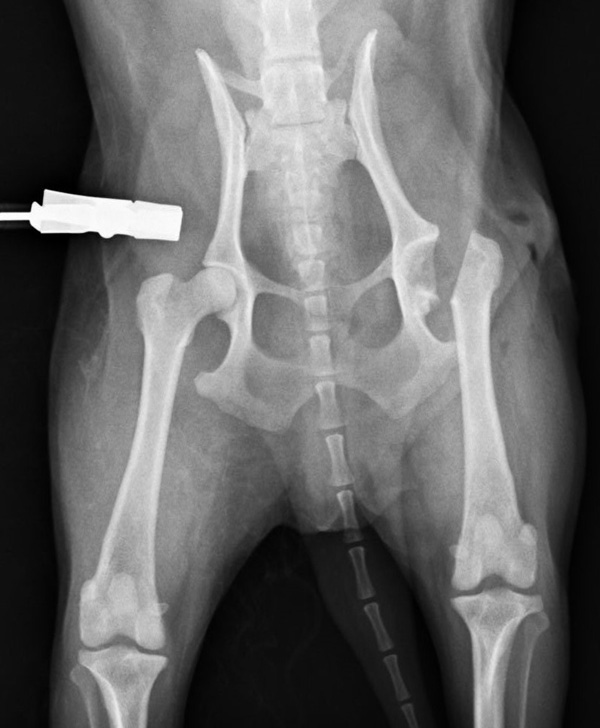

1歳未満の小型犬に多い病気です。成長期に大腿骨頭の血流が悪くなり壊死してしまう病気で、骨が変形して関節炎を起こします。これによって痛みが生じ、悪い方の後肢を上げがちになり、症状が進むと腿の筋肉が萎縮して3本足で歩行するようになります。痛みや跛行のあるものでは手術による早期治療が回復を早めるために重要です。当院では他院からのご紹介などもあり、この手術はとても多く、特にトイプードルが多いです。今回の子も無事元気に走れるようになりました。良かったね。